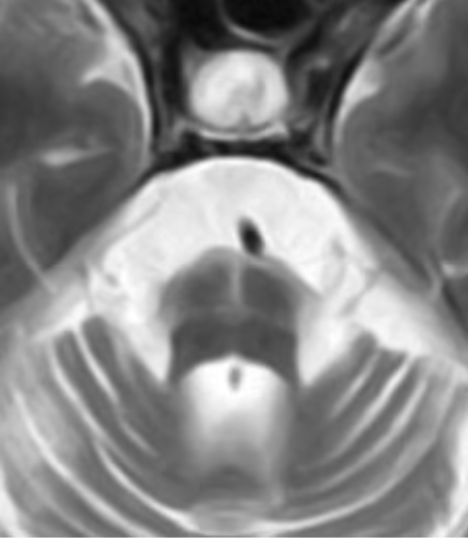

なお、軸位T2強調画像でみられる

Hot cross bun sign(HCB sign)は参考所見ですが、

MSAに特異的ではなく、

SCDなどでもみられるため注意が必要です。

Hot cross bun sign(HCB sign)

- 軸位T2/FLAIRで橋中央に「十字型」の高信号が出るサイン。

- 古典的には MSA-C に特異度が高いとされてきたが、SCA1/2/3 など SCD の一部や自己免疫性疾患でも報告されており、「MSA を強く疑わせるが、MSA に限らないサイン」として位置づけられる。